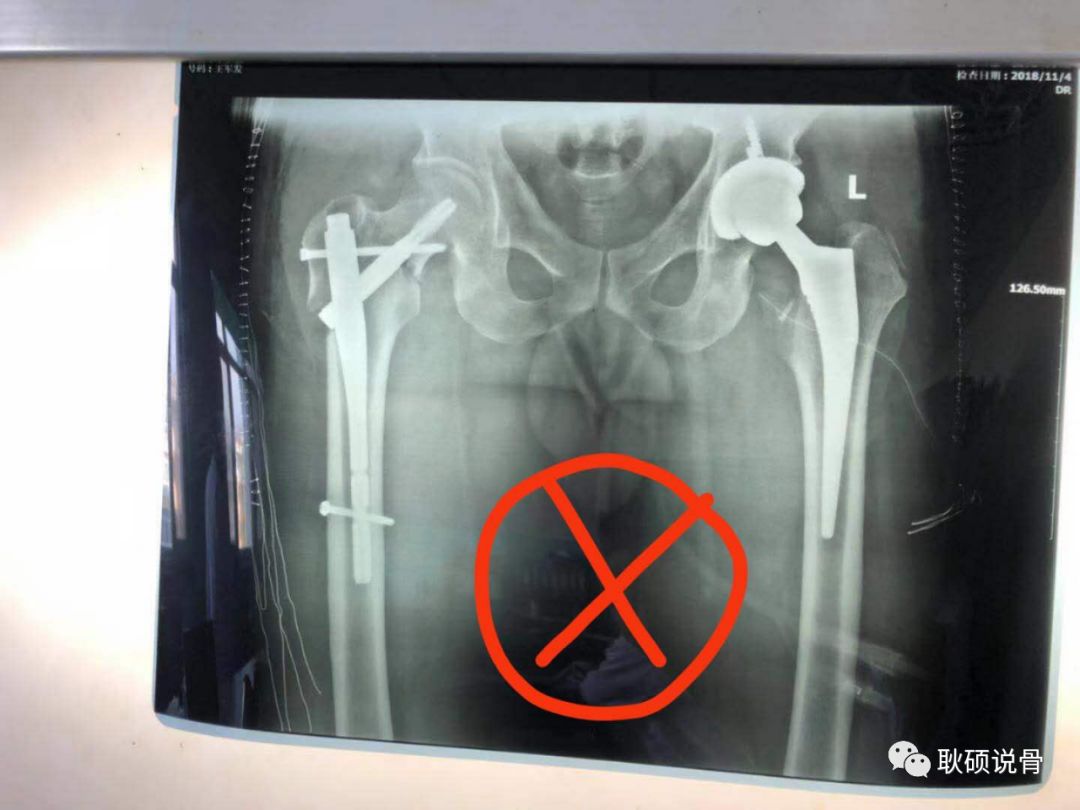

3、打开手机相机拍照!不要直接用微信拍照!调整距离拍照,保证横平竖直,整个片子内容填满整个屏幕,就像这样: